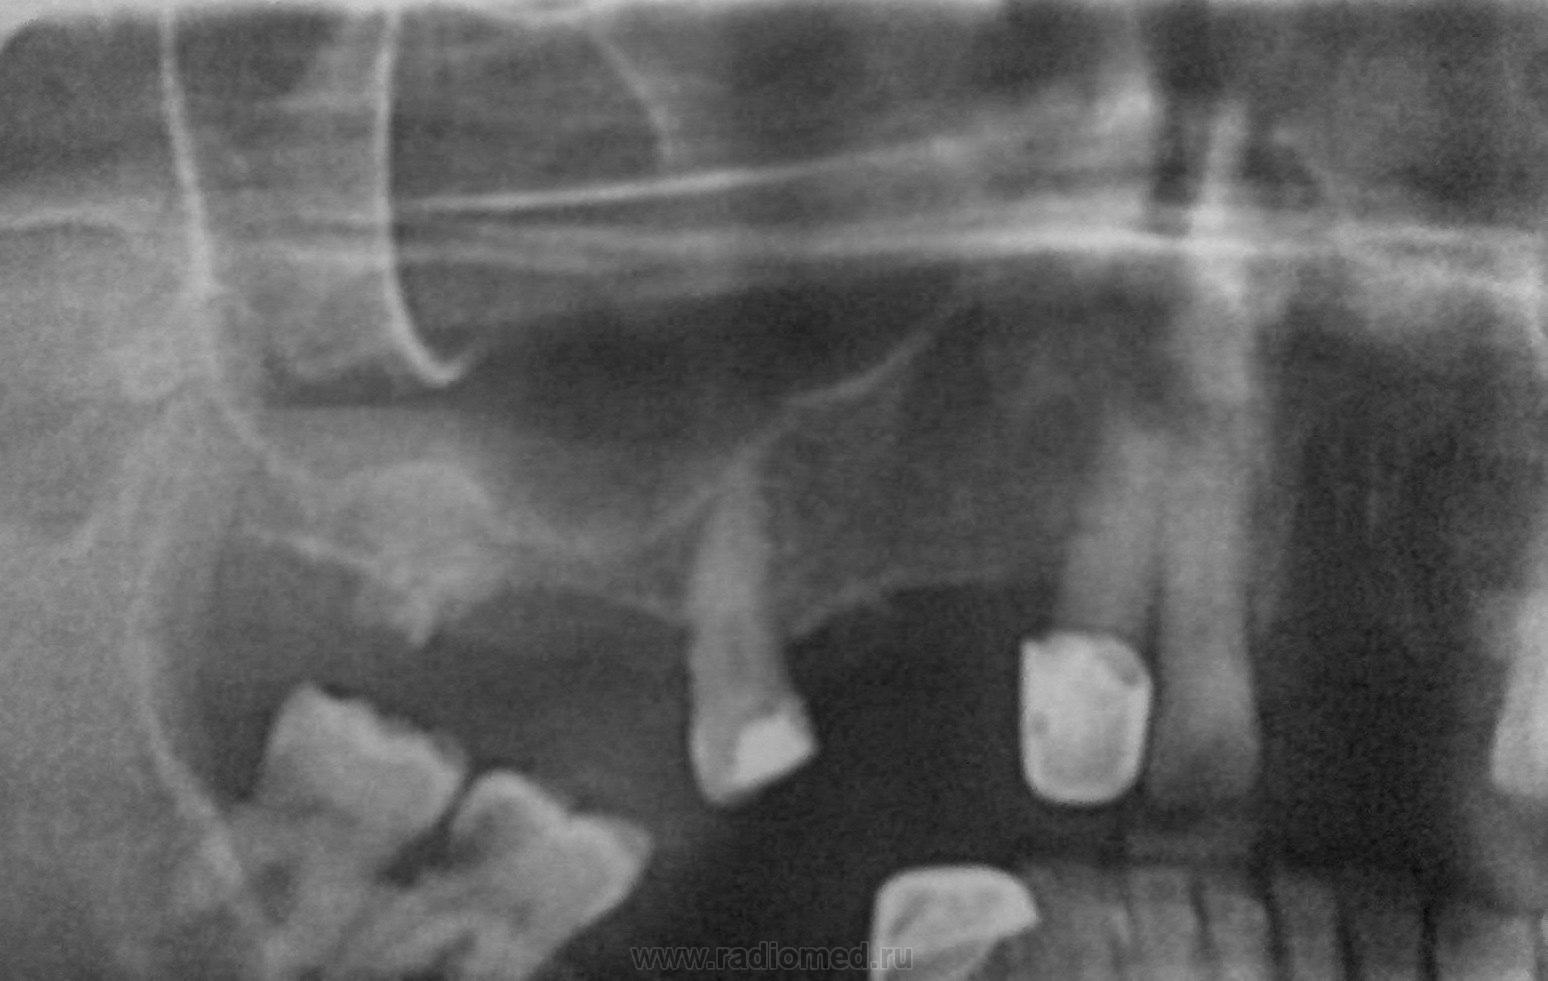

Избит. Что скажете, коллеги?

21 и 22 после избития вылетели? 18 вроде сломан. Левая половина нижней челюсти тоже не нравится.

Перелом обоих (венечного и суставного) отростков обеих ветвей  нижней челюсти. Это четыре перелома. Перелом тела нижней челюсти слева со смещением - это пятый перелом. Фрагментарный перелом альвеолярного отростка левой верхнечелюстной кости со смещением, а с ним два перелома зубов. Итого 8 переломов. Поправьте меня, вряд ли я точен. Но, все равно, - к челюстно-лицевому хирургу.

Если честно...то ничего из этого...

Т.е. перелом то есть...но верхней челюсти справа...а по поводу зубов - травматическая экстракция двух слева.

Может качество копии подвело...все таки это фото с оригинальной распечатки.

По поводу  верхних справа 1 2 - ДА, правы!)))

Правая нижняя лунка 6-ки тоже на свежую тянет.

Перелом угла челюсти и зуба мудрости), вроде еще перелом венечного отростка с той же стороны